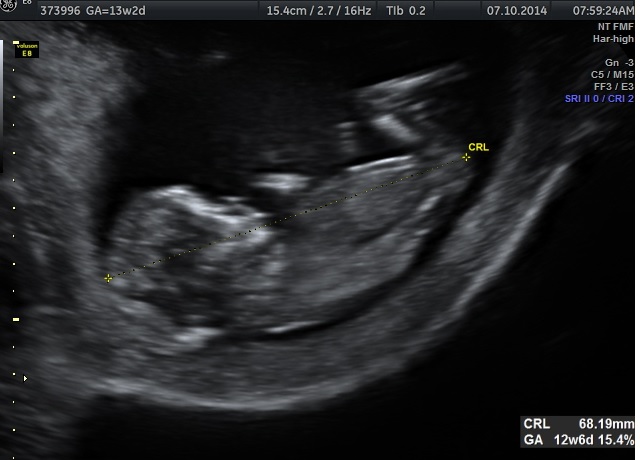

i found some 2D ones, does it help? :)

here it is again:)

Attachment 22047

Maybe maybe girl :)